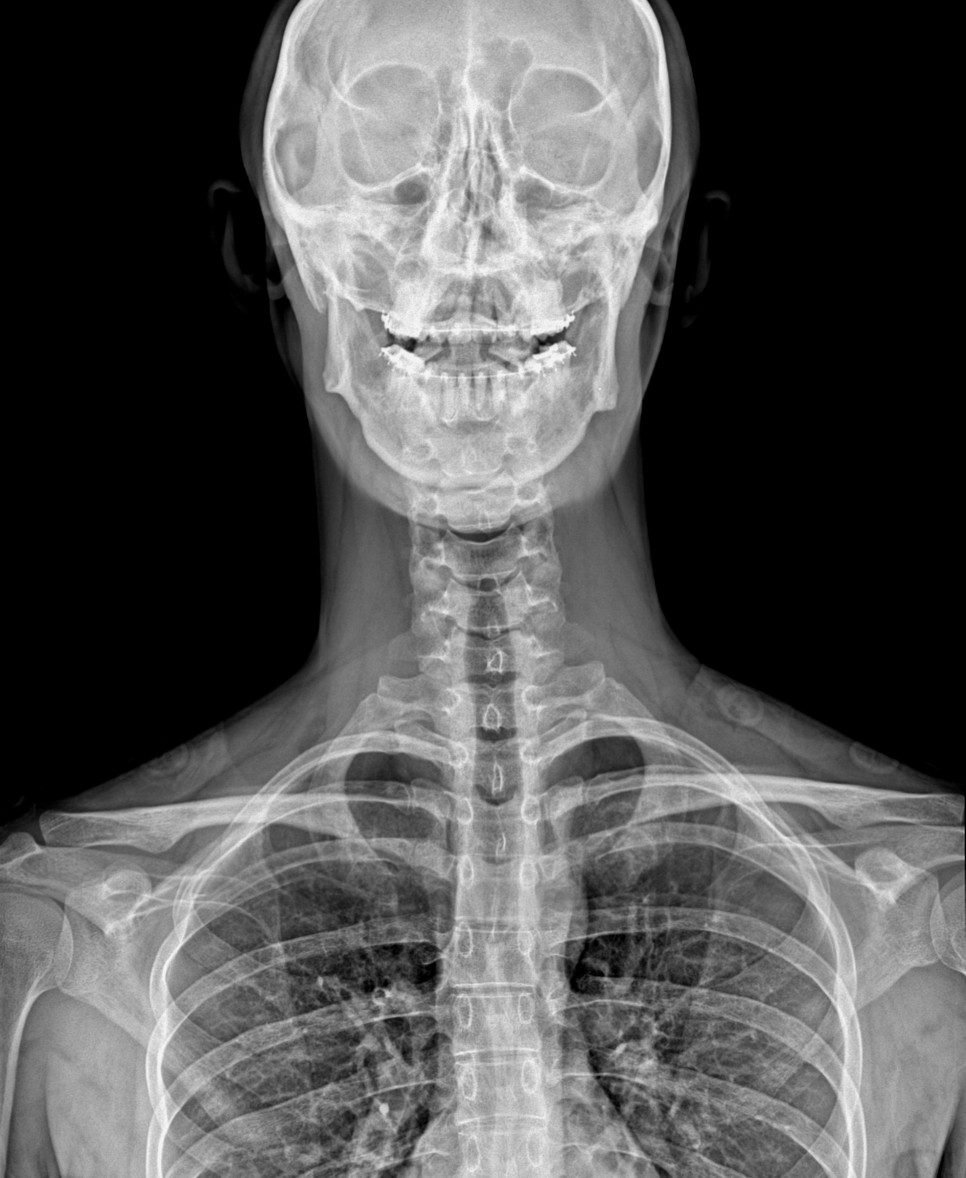

환자의 경추를 보면 정상적인 c 커브가 아니라 곧게 열린 일자 상태를 나타내고 있었습니다.

그리고 심각한 수준은 아니지만, 목의 균형이 한쪽으로 치우쳐 있는 것을 확인할 수 있었습니다.